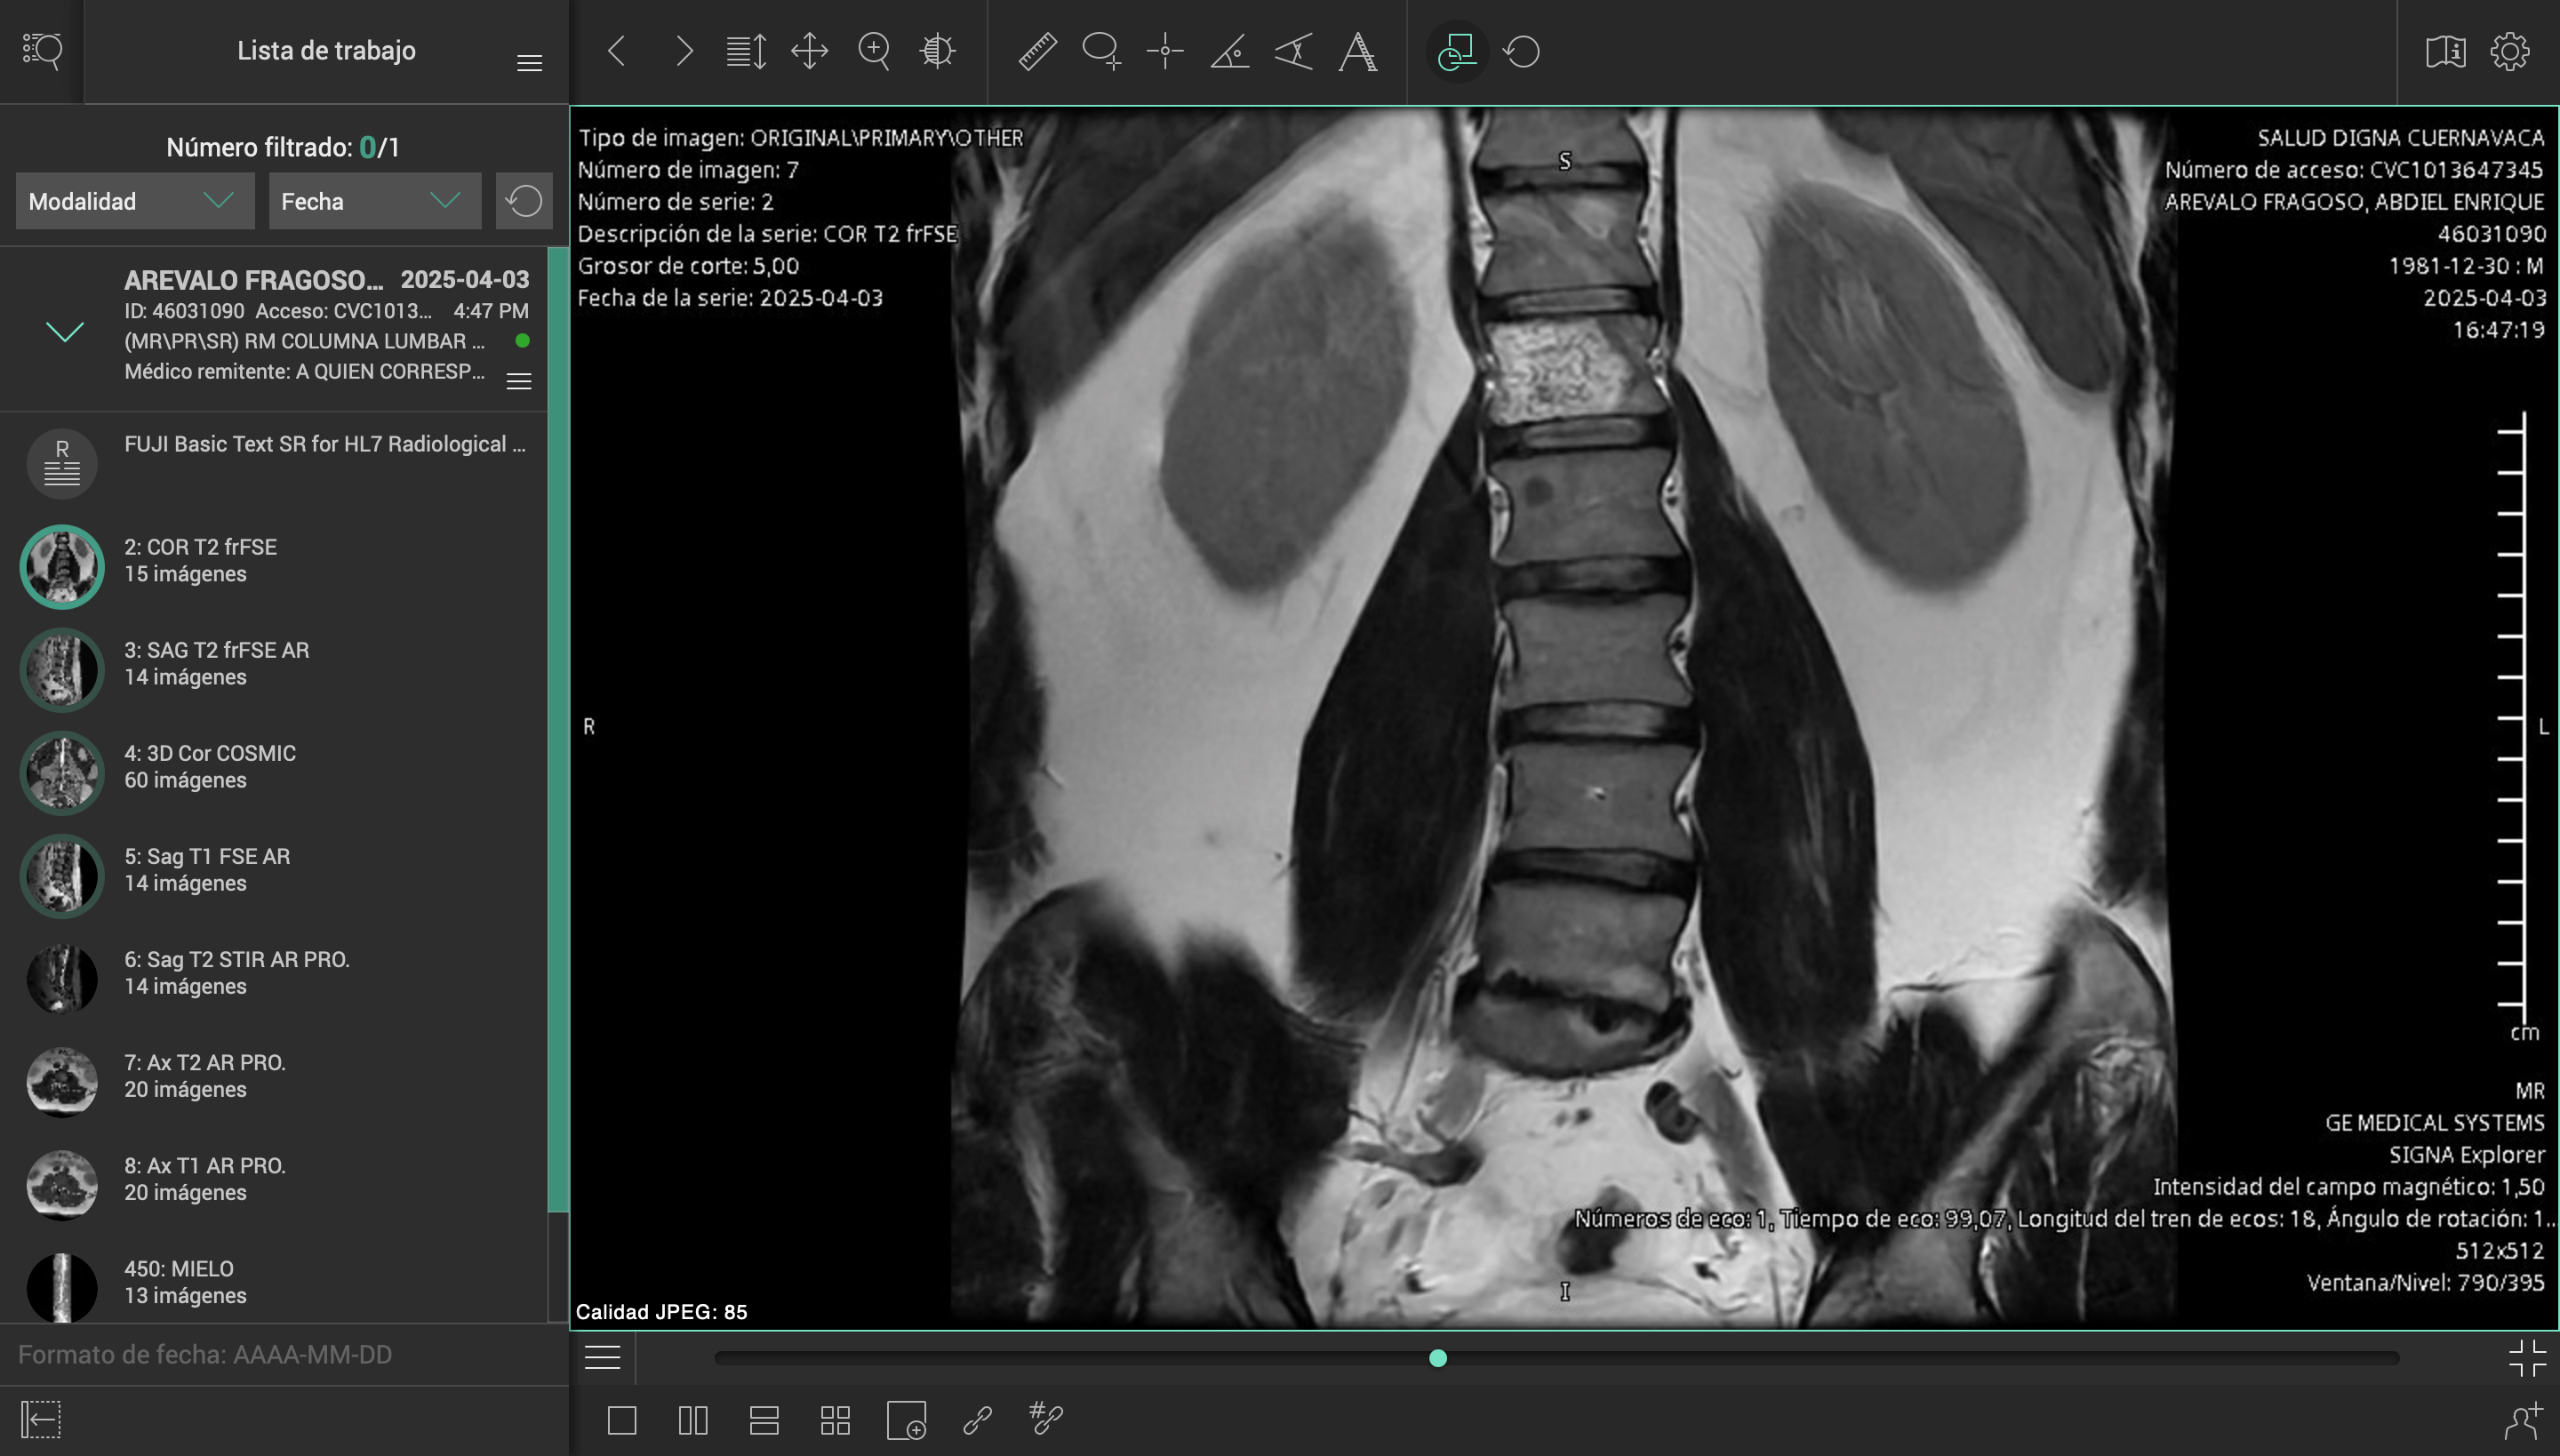

El pasado 2 de marzo de 2025, sufrí un accidente en carretera mientras conducía mi motocicleta. Un automóvil me impactó y me arrojó contra el asfalto, causándome lesiones severas en el hombro izquierdo, columna cervical y lumbar. El conductor se dio a la fuga, y hasta ahora no ha sido posible obtener justicia ni apoyo institucional.

Desde entonces, han pasado más de tres meses esperando una consulta con un especialista del ISSSTE, sin éxito. Durante este tiempo, mi salud ha empeorado, con complicaciones cada vez mayores por la falta de atención médica oportuna.

Esta situación me ha colocado en una condición muy vulnerable, médica, emocional y económicamente. Los tratamientos, terapias y cirugías necesarias superan los casi un millón de pesos mexicanos, una cifra que me resulta imposible cubrir por mi cuenta.